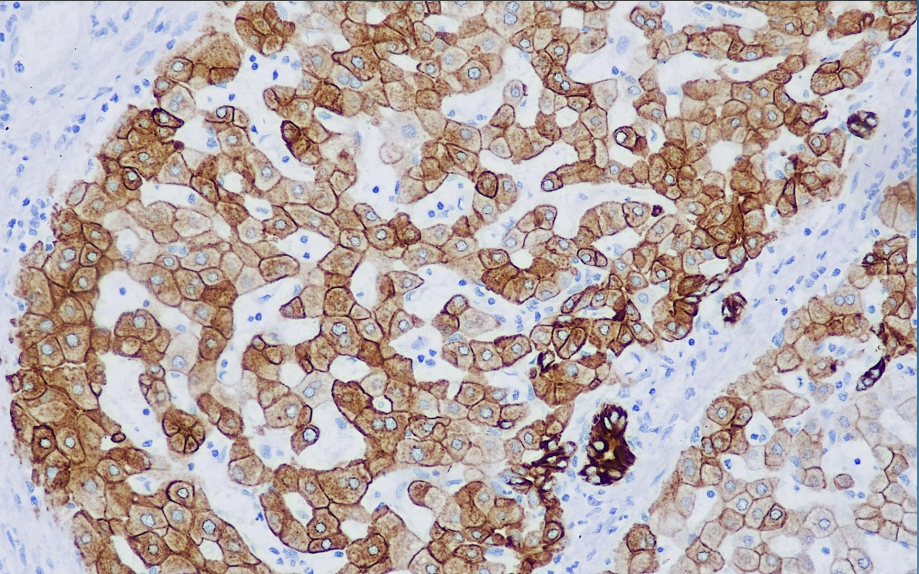

This antibody recognizes cytokeratins with molecular weights of 52 kD (CK8) and 45 kD (CK18), respectively, and primarily labels various monolayers of epithelium including glandular epithelium; squamous epithelium does not generally express such antigens. Therefore it can be used as a marker representative of glandular epithelium and tumors of its origin.

CK8&18 antibody reagents can specifically bind to CK8&18 molecular antigens. Immunohistochemistry kits containing CK8&18 antibody reagents are suitable for the auxiliary diagnosis of squamous cell carcinoma and adenocarcinoma.